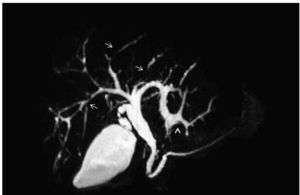

Picture showing MRCP (arrow marks )π©π»ββοΈπ¦

Answer is primary sclerosing cholangitis...